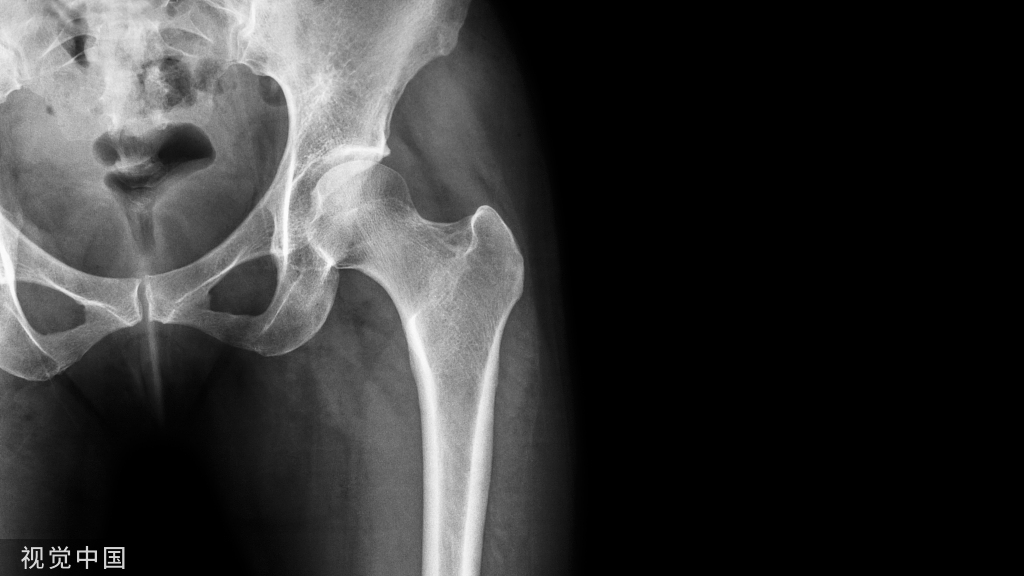

影像学检查

踝正侧位X线片显示:踝关节呈后脱位,腓骨远端呈前下后上骨折,近骨折端向后内移位,交锁于胫骨后方外侧嵴,侧位显示踝关节前侧间隙明显增宽。

二维和三维CT更能清晰显示:腓骨近折端交锁于胫骨后方的位置、程度以及骨折线走行,同时可了解其它微小骨折,后踝是否骨折,下胫腓联合的关系。